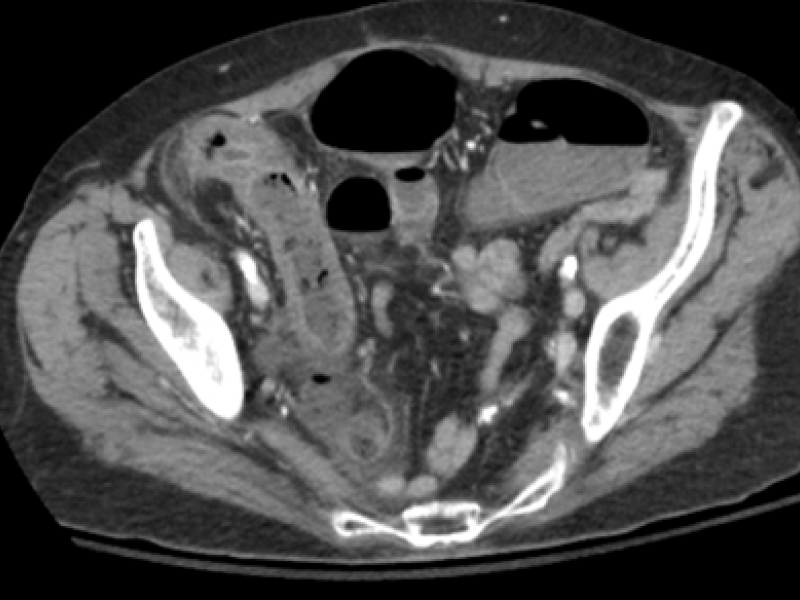

An 80 yo F with a Pmhx of HTN, AFib and atherosclerosis